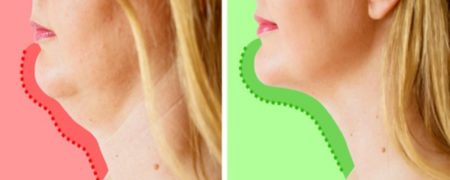

بیماری کم کاری تیروئید به ندرت علائم مشهود از خود بروز می دهد، اما همین علائم نامرئی می تواند شما را ناتوان کند! مگر اینکه بتوانید به درستی این بیماری...

علامت هشداردهنده بیماری نامرئی کم کاری تیروئید که فقط صبحها ظاهر میشود